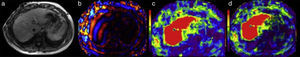

The information generated by the wavelengths that pass through the parenchyma is processed by elastography software that displays the data on a working station screen in the form of images in 4 different presentations (Table 1):

The first, is a low-resolution gray-scale reference image whose only function is to select the areas of the liver parenchyma that are to be measured, not including inadequate zones such as the portal vessels, large fissures, the gallbladder, etc. (Figure 2a).

The second image corresponds to a map of the wavelengths in color and motion that shows the advance of the wavelengths into the liver tissue (Figure 2b).

The third image, called an elastographic map, is a color map of the stiffness of the liver. A colorimetric scale is attached to each elastographic map (Figure 2c).

The elastography software creates a fourth image called the “confidence map” that outlines the zones of the liver that can be reliably measured (Figure 2d).